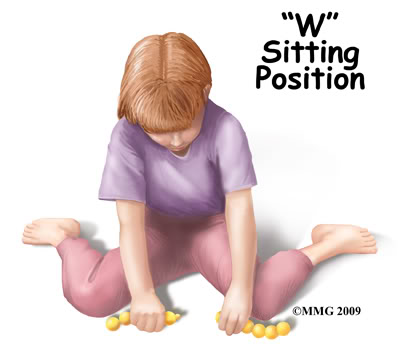

- Postura defectuoasă în special la masă și atunci când lucrează la birou

Prezența sau absența reflexelor primare sau posturale în anumite etape cheie ale dezvoltării reprezintă argumentul pentru imaturitatea în funcționarea sistemului nervos central și va influența dezvoltarea și controlul posturii, echilibrului și a funcțiilor motorii.